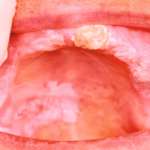

I metodi di ausilio ottico utili per l’anticipazione della diagnosi di cancro orale

Il cancro orale rappresenta una sfida significativa nel campo della salute pubblica e della medicina. Nei Paesi occidentali costituisce dal 6% al 10% di...